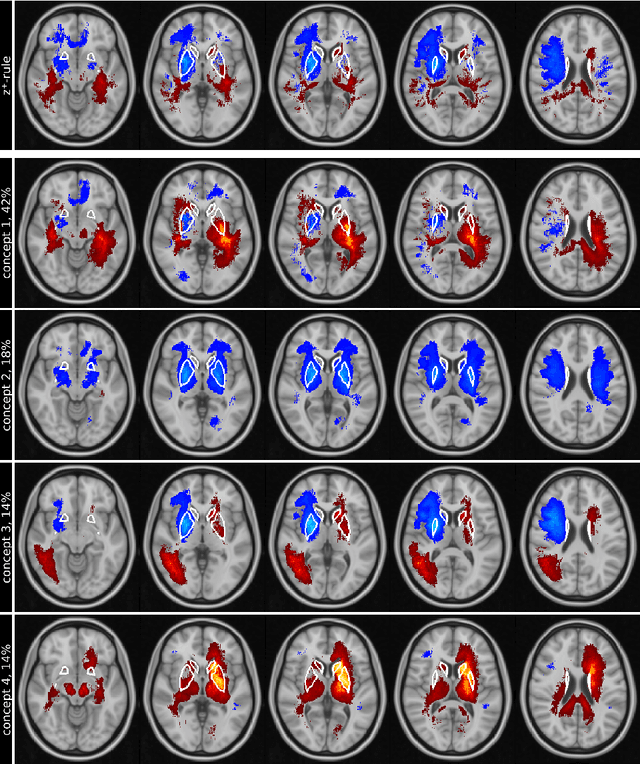

Abstract:Motivation. While recent studies show high accuracy in the classification of Alzheimer's disease using deep neural networks, the underlying learned concepts have not been investigated. Goals. To systematically identify changes in brain regions through concepts learned by the deep neural network for model validation. Approach. Using quantitative R2* maps we separated Alzheimer's patients (n=117) from normal controls (n=219) by using a convolutional neural network and systematically investigated the learned concepts using Concept Relevance Propagation and compared these results to a conventional region of interest-based analysis. Results. In line with established histological findings and the region of interest-based analyses, highly relevant concepts were primarily found in and adjacent to the basal ganglia. Impact. The identification of concepts learned by deep neural networks for disease classification enables validation of the models and could potentially improve reliability.